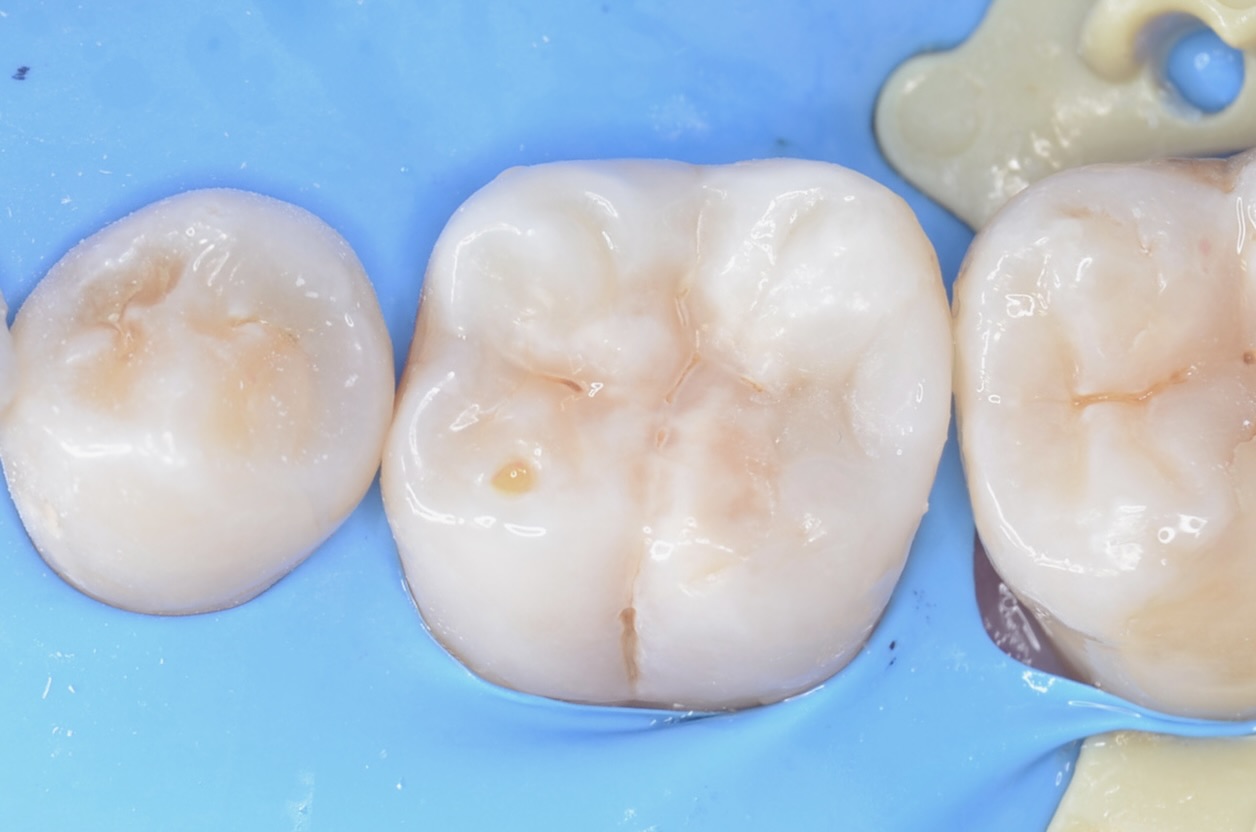

ラバーダム撤去後

噛み合わせを調整しています。 -

6番の歯の近心と頬側にも治療必要部位がありますが、次回に持ち越します。 -

セパレートゴムの装着

ゴムを入れて1週間後に治療をい続けます。 -